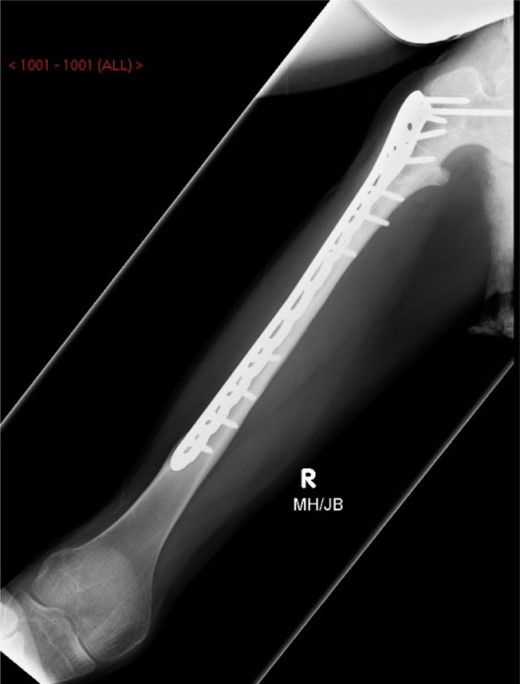

Under general anaesthesia, open reduction and internal fixation using a 10 hole philos plate was performed with the patient in a supine position on the traction table utilizing a lateral approach. Using C-arm image intensification, the height of the plate was judged, then applied to the bone and secured both proximally and distally to the fracture with proximal locking screws inserted where possible (Fig. 2a–c). Securing the cephalic segment of the philos plate to the proximal femur proved challenging due to the femoral neck defect left by the removal of the blade plate. Final reduction was judged to be near anatomical with the wound thoroughly irrigated with saline before closure. Post-operative treatment included IV antibiotics with mobility instructions unnecessary due to the patient's non-ambulatory status. The patient was discharged after 5 days with a follow-up period over 11 months. There were no post-operative complications during this time and radiographs showed an anatomically healed fracture (Fig. 3).

AP-XR demonstrating radiographic union at 11 months with 10 hole PHILOS insitu.